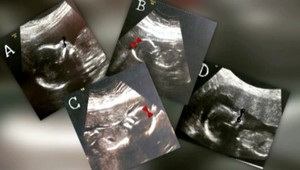

Po zrážke vlakov prežili všetci pacienti, hlási UNLP. Medzi zranenými boli aj tehotná žena a cudzinka